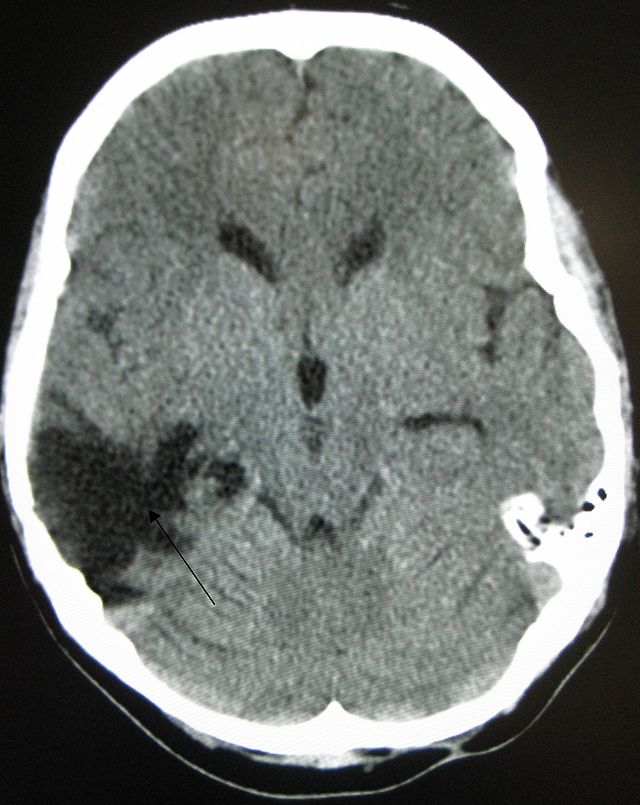

Диагностика травм головы начинается  с анализа анамнеза, проведения неврологических тестов и использования стандартного метода оценки состояния больного. Постановке точного диагноза способствуют рентгенологические исследования, КТ, МРТ, энцефалография. Проведение люмбальной пункции позволяет исследовать давление, прозрачность и состав цереброспинальной жидкости.